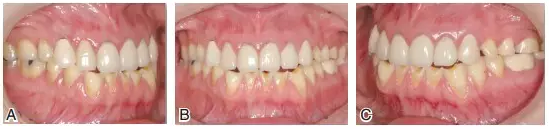

圖6患者J初診時的最大牙尖交錯位咬合情況。上頜后牙及下頜前牙區(qū)重度磨耗,后牙區(qū)牙合曲線呈上凸的倒曲線

圖7患者J初診時的下頜前伸(A)及下頜左(B)、右(C)側方運動情況??梢娫诰捉肋\動時,僅有單側上下頜前磨牙的個別點接觸,咀嚼效率差,咀嚼肌易疲勞